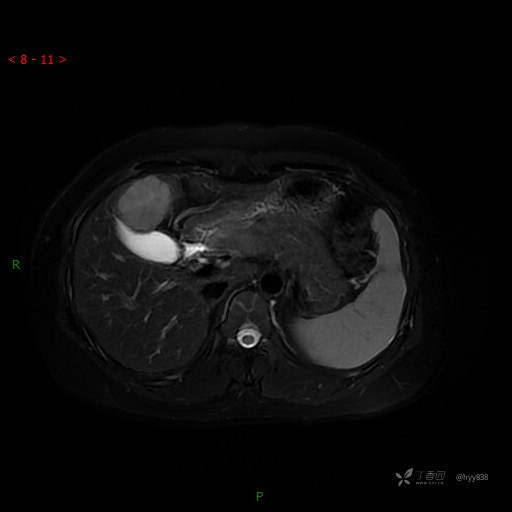

DWI